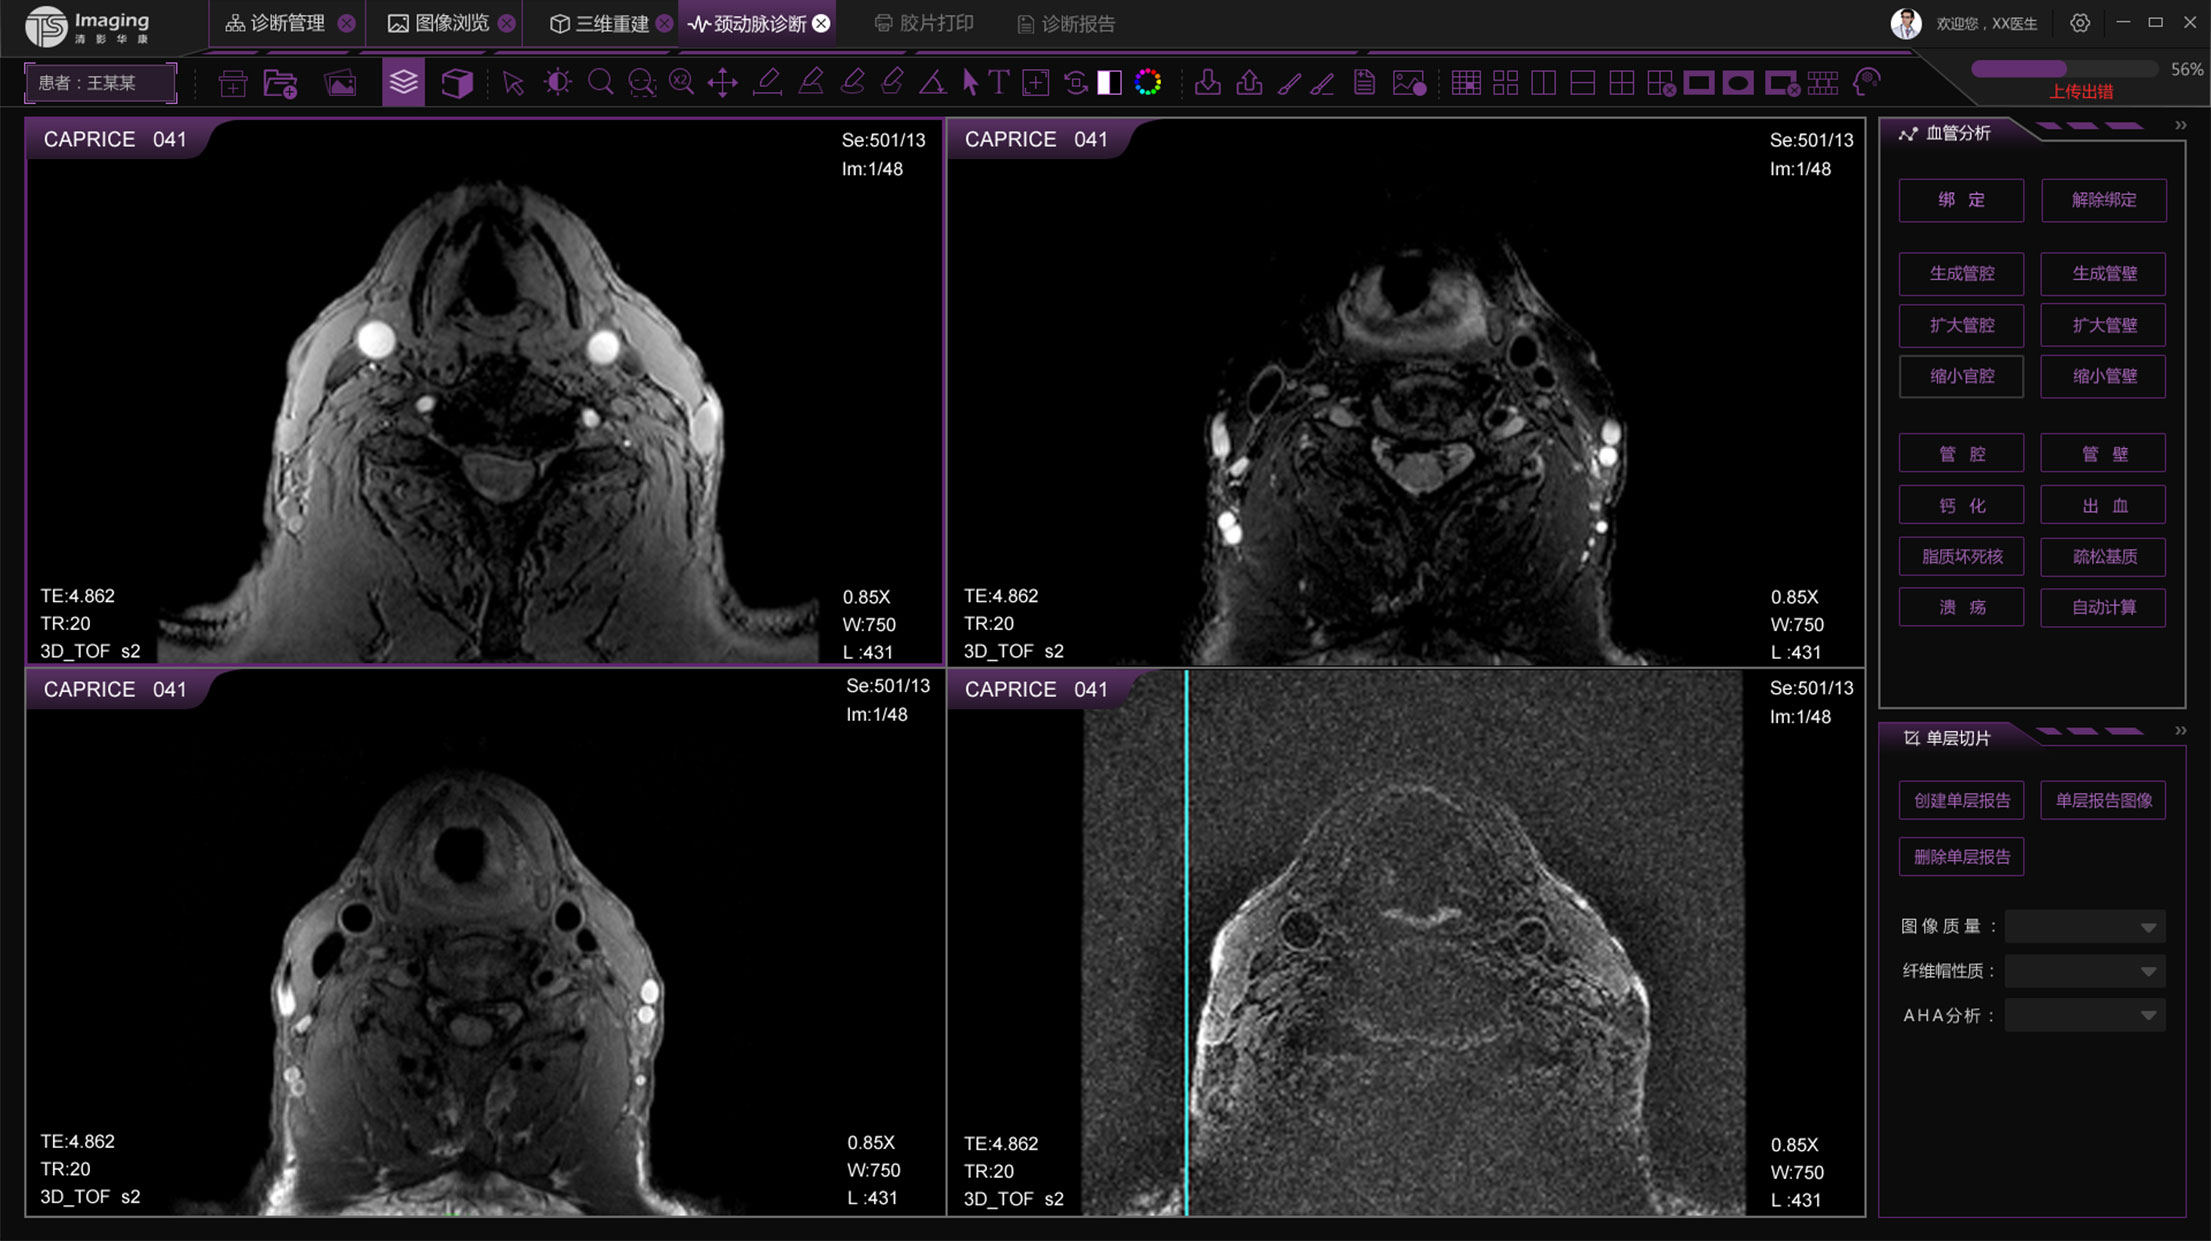

頸動(dòng)脈診斷頁(yè)面

頸動(dòng)脈診斷頁(yè)面整體布局和三維重建比較相似,最大的區(qū)別是右側(cè)的操作區(qū)域,血管分析都為按鍵操作,通過(guò)間隔的大小分成三部分。單層切片除了按鍵還有下拉菜單的操作。